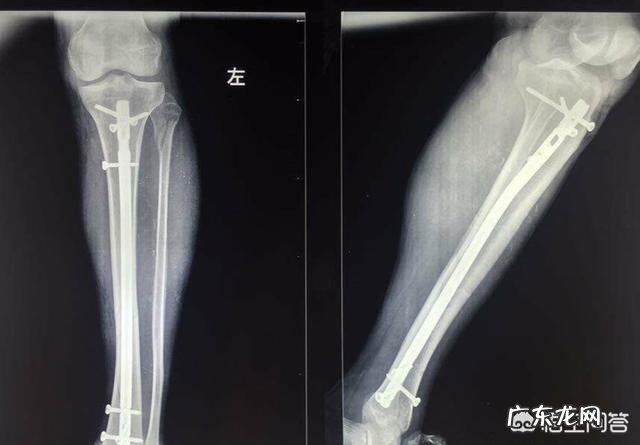

【胫腓骨双骨折,髓内钉固定手术后两个月了,是不是要去复查了?】例如,骨折端是否有骨痂生长,是否牢固,是否有内固定松动,是否可以下地走路,负重多少,每个人都不一样,如果没有复查拍片,就自行出去溜达,可能造成骨折端的移位,甚至内固定的折弯,螺丝脱落,有的问题是可以避免的,如果有点松动,我们可以用外固定补救,但移位了,内固定弯曲了,甚至折断了一般只能重新手术了,而且二次手术的不愈合率要高得多 。